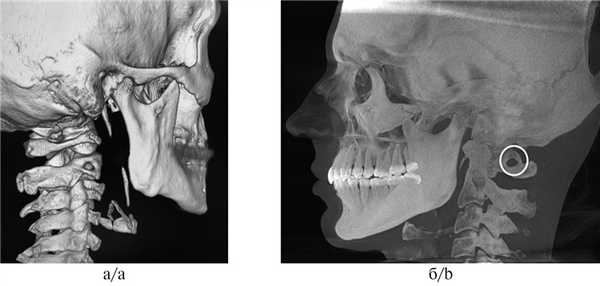

При анализе КЛКТ также можно обнаружить увеличенный шиловидный отросток вследствие оссификации шилоподъязычной связки (в норме его длина составляет 2,5—3 см, осложнение — боли при глотании, иррадиирующие в миндалины, боли в области лица, ограничение подвижности шеи, головокружение, пресинкопальные состояния, обмороки) и наличие аномалии Kimmerle (оссификация косой атланто-затылочной связки, проходящей над бороздой позвоночной артерии I шейного позвонка, осложнение — компрессия позвоночной артерии и нарушение мозгового кровообращения), что, возможно, свидетельствует о краниомандибулярных нарушениях у обследуемого. Таким образом, стоматолог может констатировать наличие шилоподъязычного синдрома и других тяжелых осложнений, ухудшающих качество жизни человека (рис.10) [15, 16].

Рис. 10. Удлиненный шиловидный отросток (а) и аномалия Kimmerle (б).